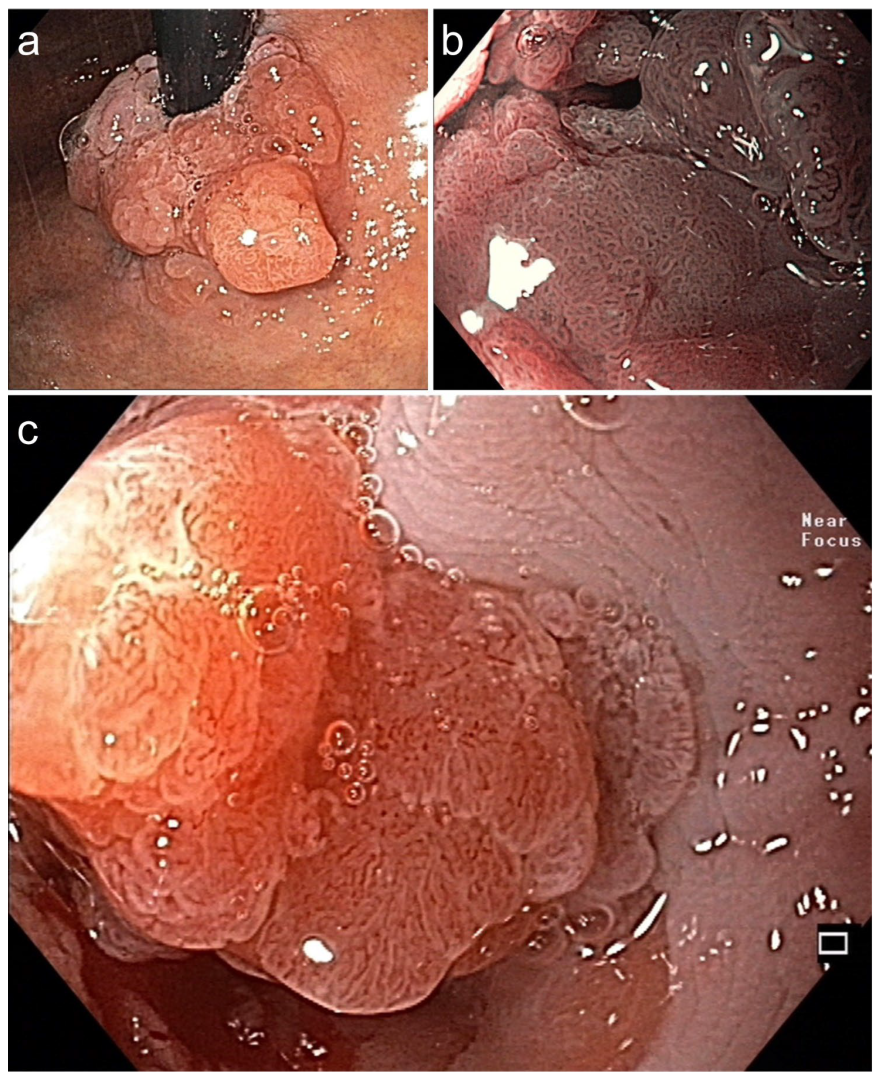

Figure 3. Symptomatic circular Barrett adenocarcinoma 0-IIa+Is for diagnostic ESD en bloc (16.6 × 6 cm). (a) in the cardia (WLI, retroflex view) and (b) in stenosis (BLI, 40×, prograde: dense VP & SP). (c) Dense SP (regular epithelial white zone) & VP with V/S concordance (WLI 60×). Histopathology: AC, G1 pT1a, m2 L0 V0 pN0 Bd1, R curative. Died at age 87 from pneumonia, DFS 5.3 yrs.

Figure 4. (a,b). Barrett adenocarcinoma 0-IIa+Is, semicircular (size 2.5 × 2 cm) in the cardia for diagnostic ESD (EUS uT1m uN0), standard WLI in prograde (a) and retroflex view (b). (c,d) A small area (0.5 cm) on the base of 0-Is with irregular SP and V/S discordance ((c) WLI 60×, (d) NBI, 60×). (e) pm-muscle retracting (MR) sign [36]. (f) Section (HE stain 100×) of AC margin showing pm invasion and resection R1 (right lower end): AC G2, pT2, R1. (Supplementary Table S3, no. 5).